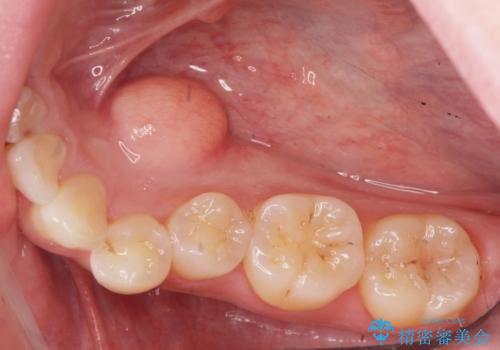

上下の歯のがたつきを改善するマウスピース矯正治療と、下顎に見られる大きな骨隆起を外科的に除去する治療計画を進めていきます。

骨隆起の除去は、静脈内鎮静法を用いてほとんど記憶のないうちに行うことができます。

歯並びが改善したとともに、骨隆起を除去したことで舌をしまうスペースも増え安定した口腔内環境を確立することができました。